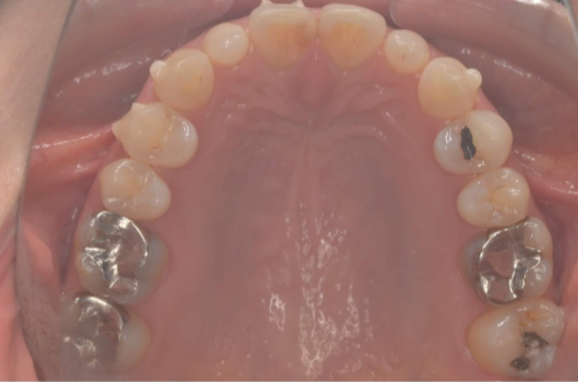

セラミック 2021.0930代女性「銀歯をすべて白くしたい」E-maxセラミックと保険のレジンで白くした症例